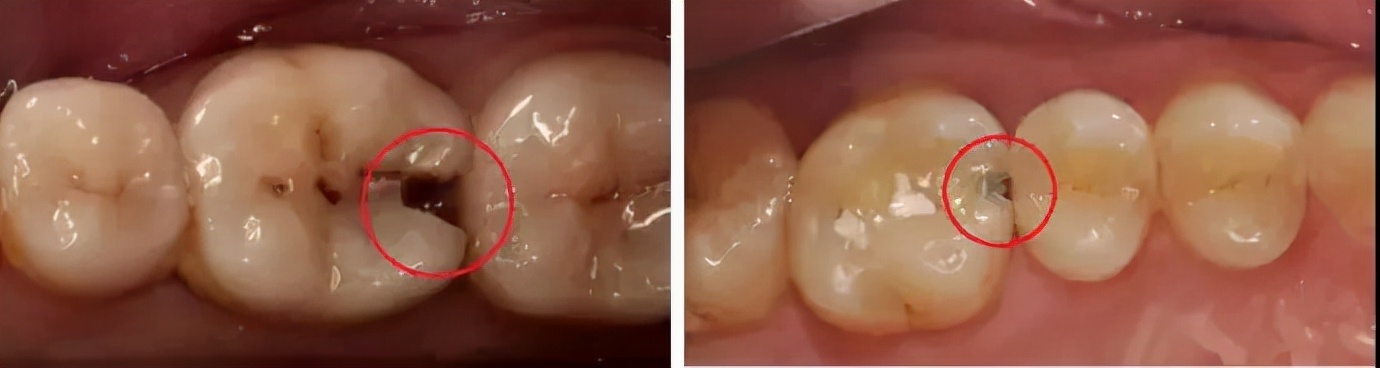

最磨人的龋要数那种白色、米黄色的。这类龋和牙齿本来的颜色非常接近,如果不是定期的去医院检查牙齿,或者已经疼痛根本不知道它们的存在,肉眼是非常难发现的,而且通常这种龋,坏牙速度非常快。

龋齿的发展是有阶段的,不同阶段有不同的补救措施,但是如果已经龋坏到牙髓,就只能杀神经或者拔牙了。

浅龋:牙齿表面有黑点或者黑线,日常饮食作息都不会出现疼痛现象,龋坏只破坏了牙釉质。

补救措施:把赃物清理干净,通过普通的补牙即可。

中龋:龋坏到牙本质,牙齿遇冷遇热遇甜等会有刺激性疼痛,刺激停止刺痛也停止。

补救措施:在没有穿透到牙髓腔时,清理干净补上就可以。

深龋:细菌到达牙本质深层,接近牙髓,咬东西时会感到刺痛,疼痛感会反复出现。

补救措施:这个时候无法直接补牙了,需要做根管治疗处理。龋坏缺损较大时可以通过根管治疗+补牙,前牙根管+普通树脂,后牙根管+嵌体修复或者根管+进口树脂。